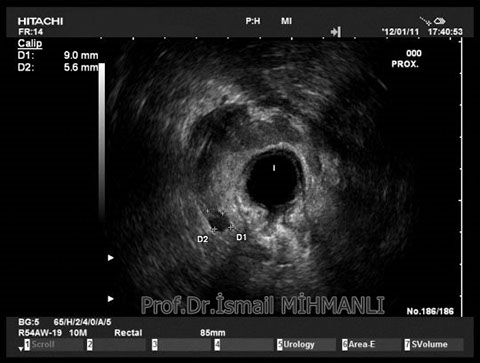

Transsfinkterik fistül

Fistüle makat kası hasarı eşlik ediyorsa endoanal US'de tespit edilir.